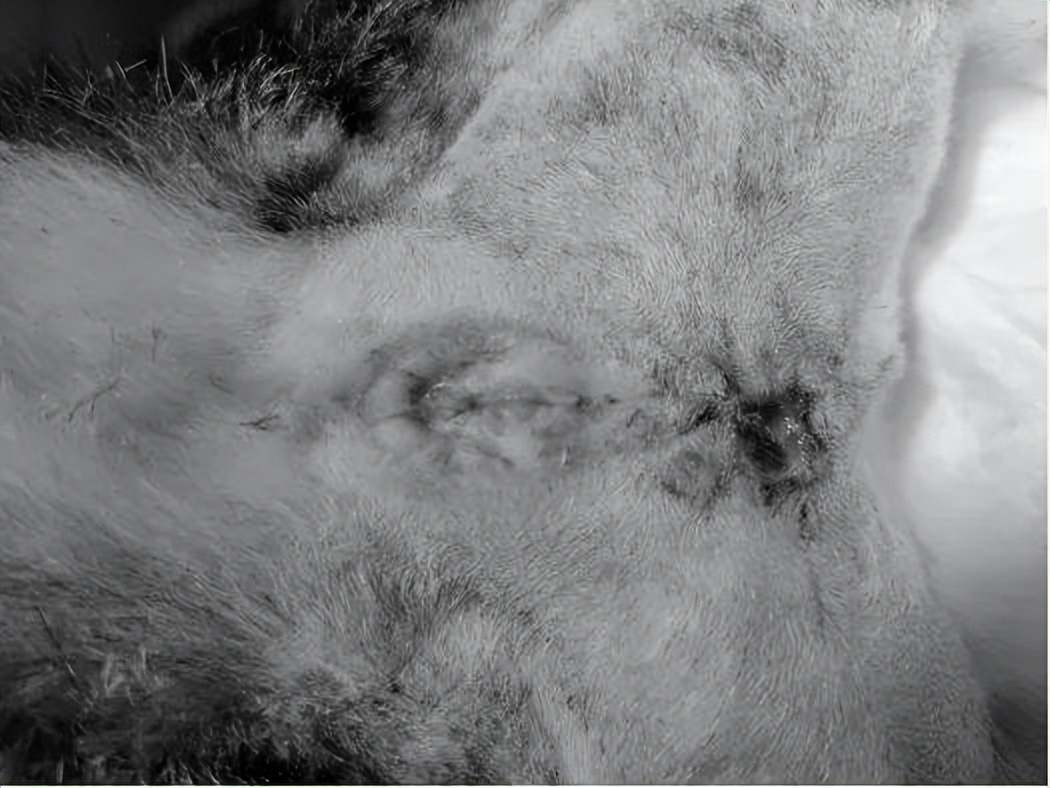

就诊时发现尿道口已闭合,膀胱壁增厚,且内有强回声物质,尿检大量炎性细胞且有吞噬细菌

一周后尿道口情况

术后四周尿道口情况